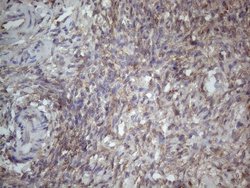

MTF1 Monoclonal Antibody for Western Blot, IHC (P)

| Immunohistochemistry (Paraffin), Western Blot | |